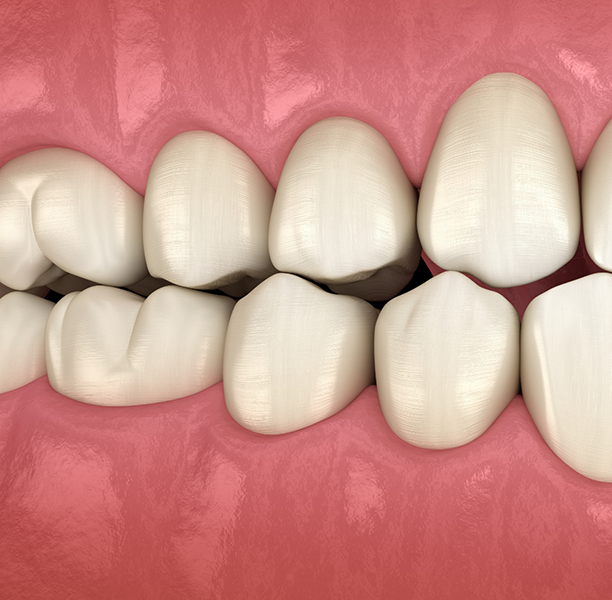

Dentistry is an exciting, ever-changing field. Experts have varying opinions on a wide range of topics, particularly occlusion. Occlusion refers to the way the teeth contact one another, both when the mouth is at rest (static occlusion) and when a person is chewing (dynamic occlusion).

For example, if Dr. Lamberti is designing a crown for a dental implant, he does more than make sure the crown fits in well with the teeth that are adjacent to it. He also considers the position of the opposing tooth (or teeth). If the opposing tooth has shifted out of its anatomically correct position, an interference results, and bite forces are incorrect. This affects both the crown’s long-term viability and the patient’s biting function capability.